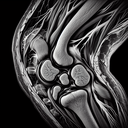

МРТ колінного суглобу

МРТ колінного суглобу – це неінвазивний метод діагностики, що використовує магнітні поля і радіохвилі для отримання детальних зображень внутрішніх структур коліна. Ця процедура допомагає лікарям виявити різні патології, такі як розриви зв'язок, пошкодження менісків, артрит, пухлини та інші проблеми м’яких тканин і кісток. **Переваги МРТ коліна:** 1...